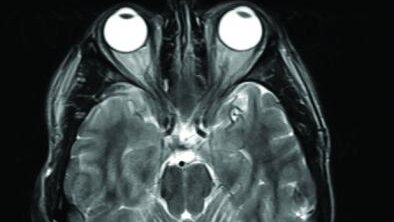

Магнитно-резонансная томография с контрастированием - это процедура внутривенного введения специального контрастного вещества на основе гадолиния пациенту для улучшения дифференциации внутренних тканей и органов, а также для визуализации изменений, не выявленных при обычном (“нативном”) исследовании без контраста. Магнитно-резонансная томография с контрастированием - это процедура внутривенного введения специального контрастного вещества на основе гадолиния пациенту для улучшения дифференциации...

Контрастное вещество - это препарат, который используется для улучшения видимости внутренних структур организма при проведении магнитно-резонансной томографии. Контрастная среда увеличивает точность диагностики...